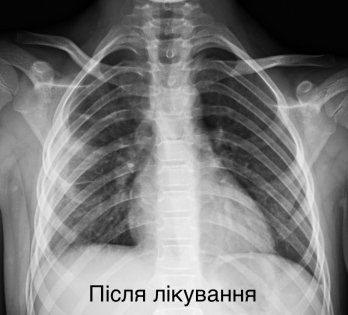

У Львові медики врятували життя дитини, яку екстрено доставили у критичному стані з деструктивною пневмонією правої легені. Дівчинка була у важкому стані: мала високу температуру тіла, задишку та низьку сатурацію кисню у крові. Про це повідомила Лікарня “Охматдит” у п’ятницю, 21 листопада.

7-річну пацієнтку одразу госпіталізували до клініки торакальної хірургії. Медики розпочали інтенсивну терапію, призначивши два сильні антибіотики, інфузійну та кисневу підтримку. Медична команда виконала тораскопічну операцію — малоінвазивне втручання, яке дозволило зберегти легеню.

“Лише через 2 розрізи розміром до 1 см ми дісталися до ураженої легені, усунули гнійно-некротичні вогнища і зберегли легеню”, — зазначив торакальний хірург Олександр Колодій.

Після операції пацієнтка перебувала у реанімації та отримувала підтримку на апараті ШВЛ.

Зараз дівчинка самостійно дихає та активно відновлюється.